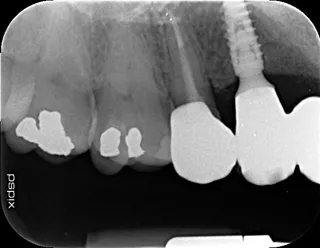

2a-b-c. Initial X-rays. The cause of the endodontic lesions was obvious, and they are underestimated on these retro-alveolar X-rays.

17a-b-c-d. Retro-alveolar X-rays at the end of treatment. Note bone behavior around the 4 implant collars. Soft tissue height above each collar was 3 to 4 mm.